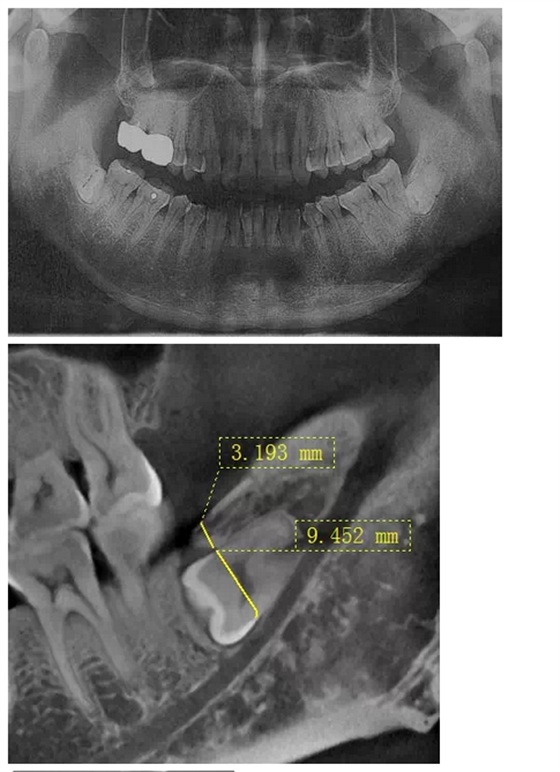

曾有這樣一位痛苦的中年患者,因雙側(cè)胸悶不適困擾二十余年,多處求醫(yī)無果,一次偶然體檢的機會,拍得口腔曲面體層片(全景片,圖一),顯示下頜雙側(cè)各有一顆水平埋伏阻生智齒,醫(yī)生建議擇期拔除。但患者更關(guān)心此二顆智齒是否是引起自己不適癥狀的原因,均被告知不敢肯定,無法從西醫(yī)角度解釋有何關(guān)聯(lián)。但痛苦驅(qū)使著患者自己去查閱了大量中醫(yī)資料,查得此下頜角處為一穴位,患者遂認為可能是這二顆牙齒點中了此穴,導(dǎo)致自己胸悶不適,說服自己之后,來我院就診要求拔除。

沒有CT,在全景片上評估右下智齒與下牙槽神經(jīng)管距離很近,告知各樣風(fēng)險,患者表示理解并簽字。常規(guī)手術(shù)切口,翻瓣,露得一部分牙冠,去骨后,多次小心翼翼檢查車針深度,使冠根分離,去除牙冠,進入取根階段,多次輕力試挺,均無動靜,只知牙根與下牙槽神經(jīng)管很近,卻不知具體的三維關(guān)系,所以只好小心翼翼地找間隙,此舉進展龜速,如履薄冰,筋疲力盡,猶如兩驅(qū)小轎車行駛在泥濘的小道上,想給力卻打滑。后來還是團隊的力量,輪番上陣,最終全部拔除,拔除后才得知原來是兩個牙根向內(nèi)直角彎曲,牢牢卡住了中間的牙槽中膈。患者第二天雖然術(shù)后反應(yīng)較大,但是非常開心地告訴我們右側(cè)胸悶有明顯好轉(zhuǎn),而且右側(cè)嘴唇?jīng)]有麻木,所以要求傷口恢復(fù)好之后馬上將左側(cè)的智齒拔除。這給我們帶來了安慰的同時,也給了我們更大的挑戰(zhàn)。

在拔牙一月后,鳥槍換大炮,診所引進了三維CT,左側(cè)智齒在拍了CT后,前后頰舌上下關(guān)系就一目了然,此牙更難拔除,因為完全埋伏(圖二),其上面覆蓋有3mm厚的牙槽骨,其下緣與下牙槽神經(jīng)管緊緊相連,較危險;牙冠前緣與第二磨牙遠中根也緊緊相連,后緣牙根向上翹;整個牙齒偏頰側(cè),頰側(cè)皮質(zhì)骨板較厚(圖三),舌側(cè)骨板也較厚,測好牙冠頸部上下距離約為9.5mm。